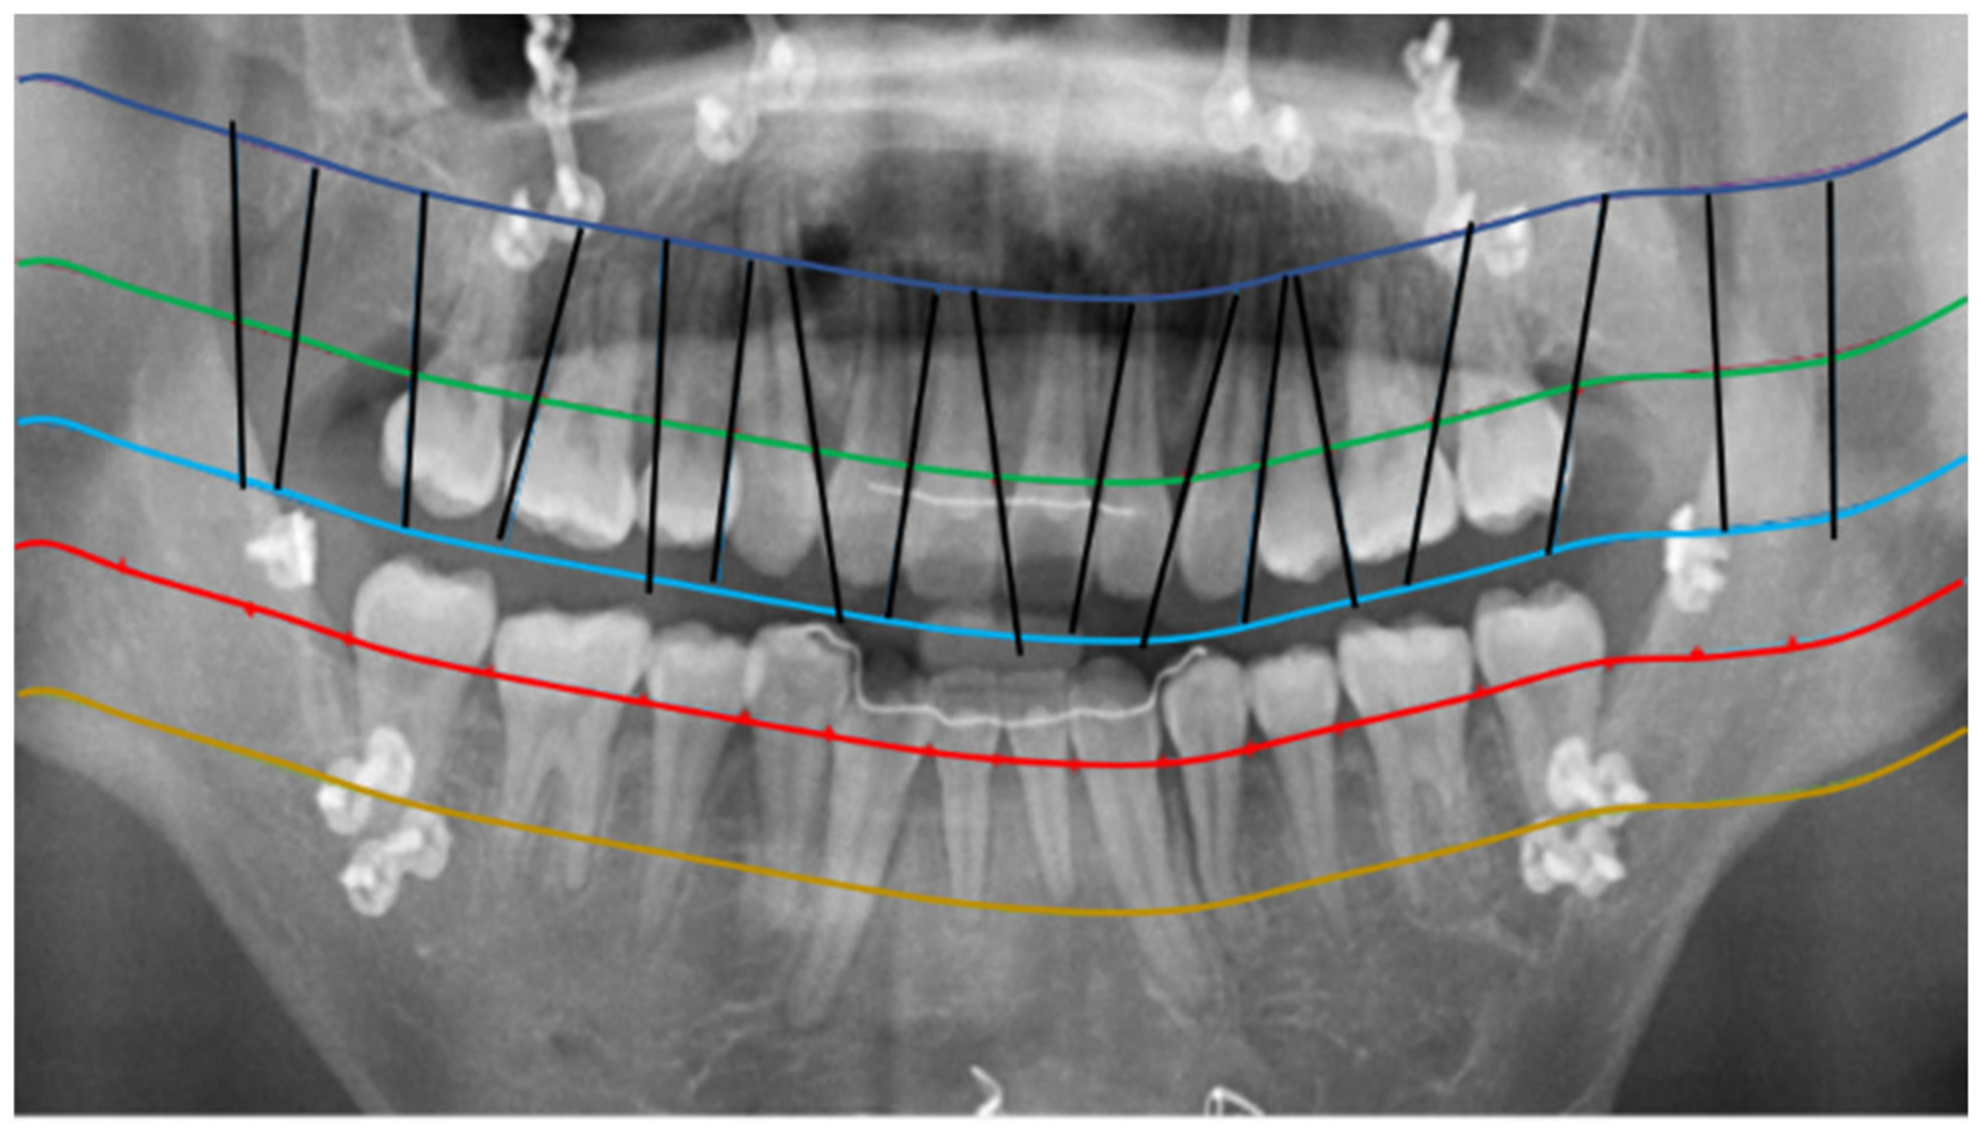

2.2.1. Curve of the Mouth

2.2.2. Curve Adjustment

2.2.3. Positioning Numbers